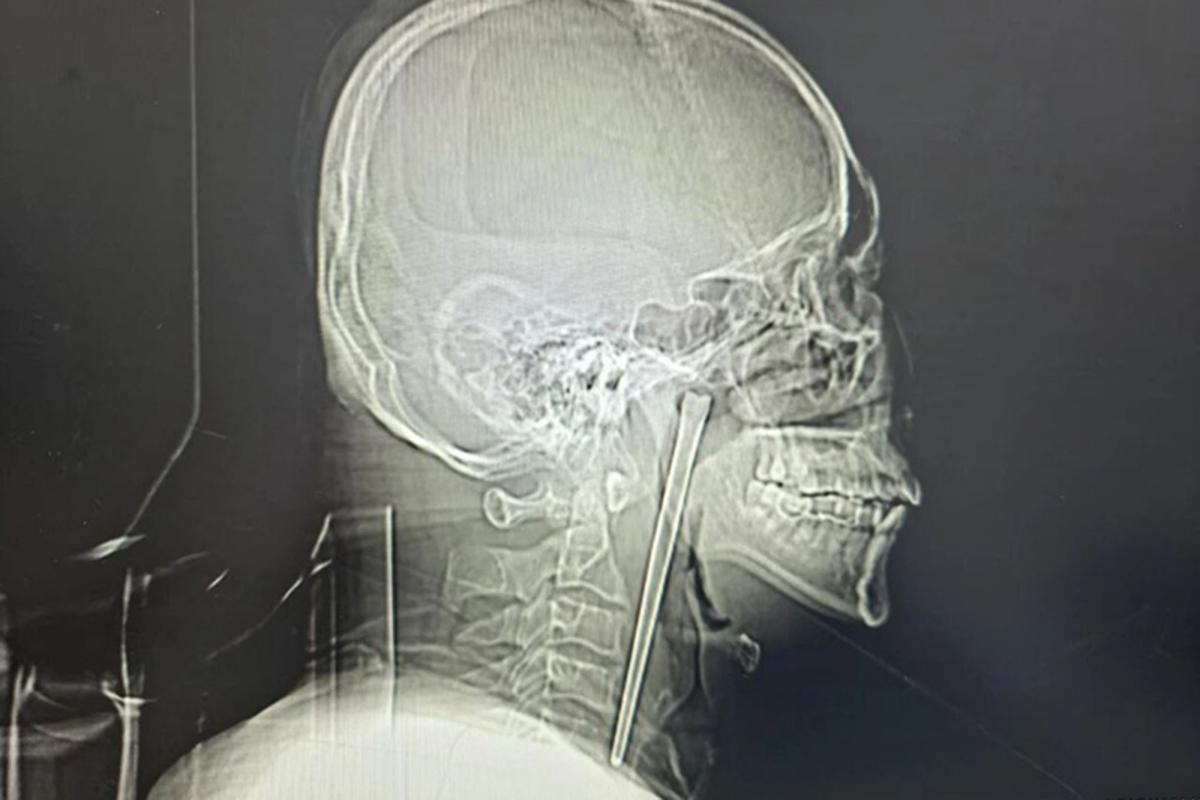

The Commissioner of Police in Enugu State, Mr Mohammed Aliyu, says the police have arrested five suspects in connection with the violence that erupted at the New Artisan Market, Enugu.…